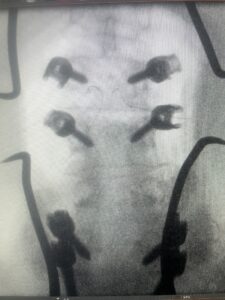

The next patient is a 54 year-old male who presents with 3 years of neck pain with associated numbness and tingling of his extremities. Patient had had physical therapy, chiropractic care, and epidural steroid injections with no significant relief. The patient on exam had weakness in a long tract distribution on the left. MRI revealed four level disc disease from C3-4 to C6-7 with a moderate kyphosis and cord compression and signal change at C3-4 (Fig. 9). Because of the kyphotic deformity it was decided to perform a four-level anterior cervical discectomy and interbody cage at each segment as well as plate. The patient had significant osteophyte disease at each level which required a high-speed drill to shave down the osteophytic disease and remove and decompress the foramina with fine Kerrison. Intraoperative imaging revealed good placement of the cages and plate at each level (Fig. 10). The patient had good relief of his preoperative symptoms.

Fig 10a and 10b: Lateral cervical x ray demonstrating placement of C3-C 7 interbody cages and plates.